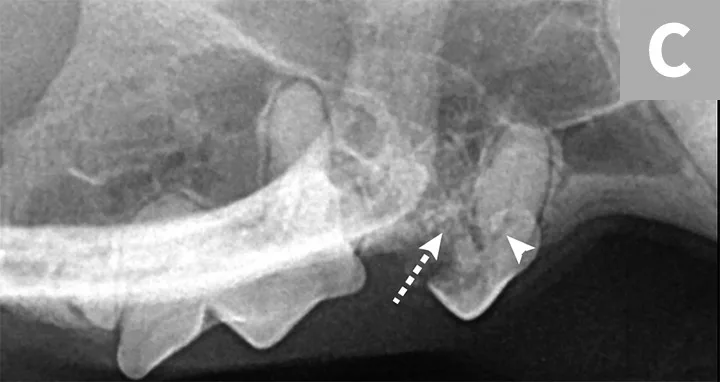

Tooth resorption type is determined via intraoral radiography based on root opacity and periodontal ligament space (see Types of Tooth Resorption Based on Radiographic Appearance and Figure 2).

Radiograph of a left mandibular molar tooth in a cat with Type 1 resorption (A) in which focal or multifocal radiolucency can be seen with otherwise normal radiopacity and normal periodontal ligament space. Radiograph of mandibular incisors and canine teeth in a cat with Type 2 resorption (B; white arrow) in which narrowing or disappearance of periodontal ligament space is present in at least some areas, and part of the tooth demonstrates decreased radiopacity. Radiograph of the right maxillary third and fourth premolars in a cat with Type 3 resorption (C); the third premolar features Type 1 resorption of the mesial root (arrowhead) and Type 2 resorption of the distal root (dashed arrow) with exposure to the oral cavity.

Type 1 (T1): focal or multifocal radiolucency in a tooth with otherwise normal radiopacity and normal periodontal ligament space

Type 2 (T2): decreased radiopacity in part of a tooth with narrowed or absent periodontal ligament space in at least some areas

Type 3 (T3): features of Type 1 and Type 2 in the same tooth; focal or multifocal radiolucency in a tooth and decreased radiopacity in other areas of the tooth with areas of normal and narrow or lost periodontal ligament space